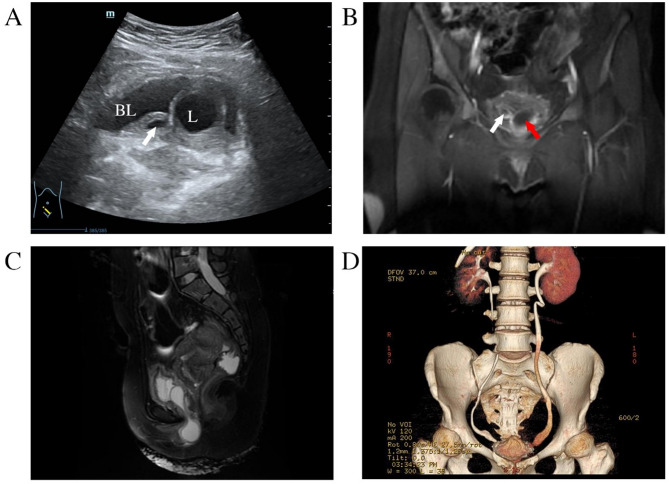

Case presentation: A 37-year-old female presented with a one-year history of recurrent urinary symptoms, including frequent urination, urgency, and dysuria. Over the past two months, she noticed a prolapsed vulvar mass accompanied by urinary incontinence. Three weeks prior to admission, she underwent tension-free vaginal tape-obturator (TVT-O) surgery at another hospital for presumed stress urinary incontinence (SUI). Three days ago, the vulvar mass increased to the size of an egg and could not be manually reduced, accompanied by straining during voiding. Ultrasound and MRI revealed bilateral ureteroceles, with the left ureterocele prolapsed from the bladder to the urethral opening. A diagnosis of ureterocele prolapse with incarceration was made, and the patient underwent manual reduction followed by cystoscopic resection of the left ureterocele. Two days postoperatively, she developed acute pyelonephritis, which was successfully treated with antibiotics.